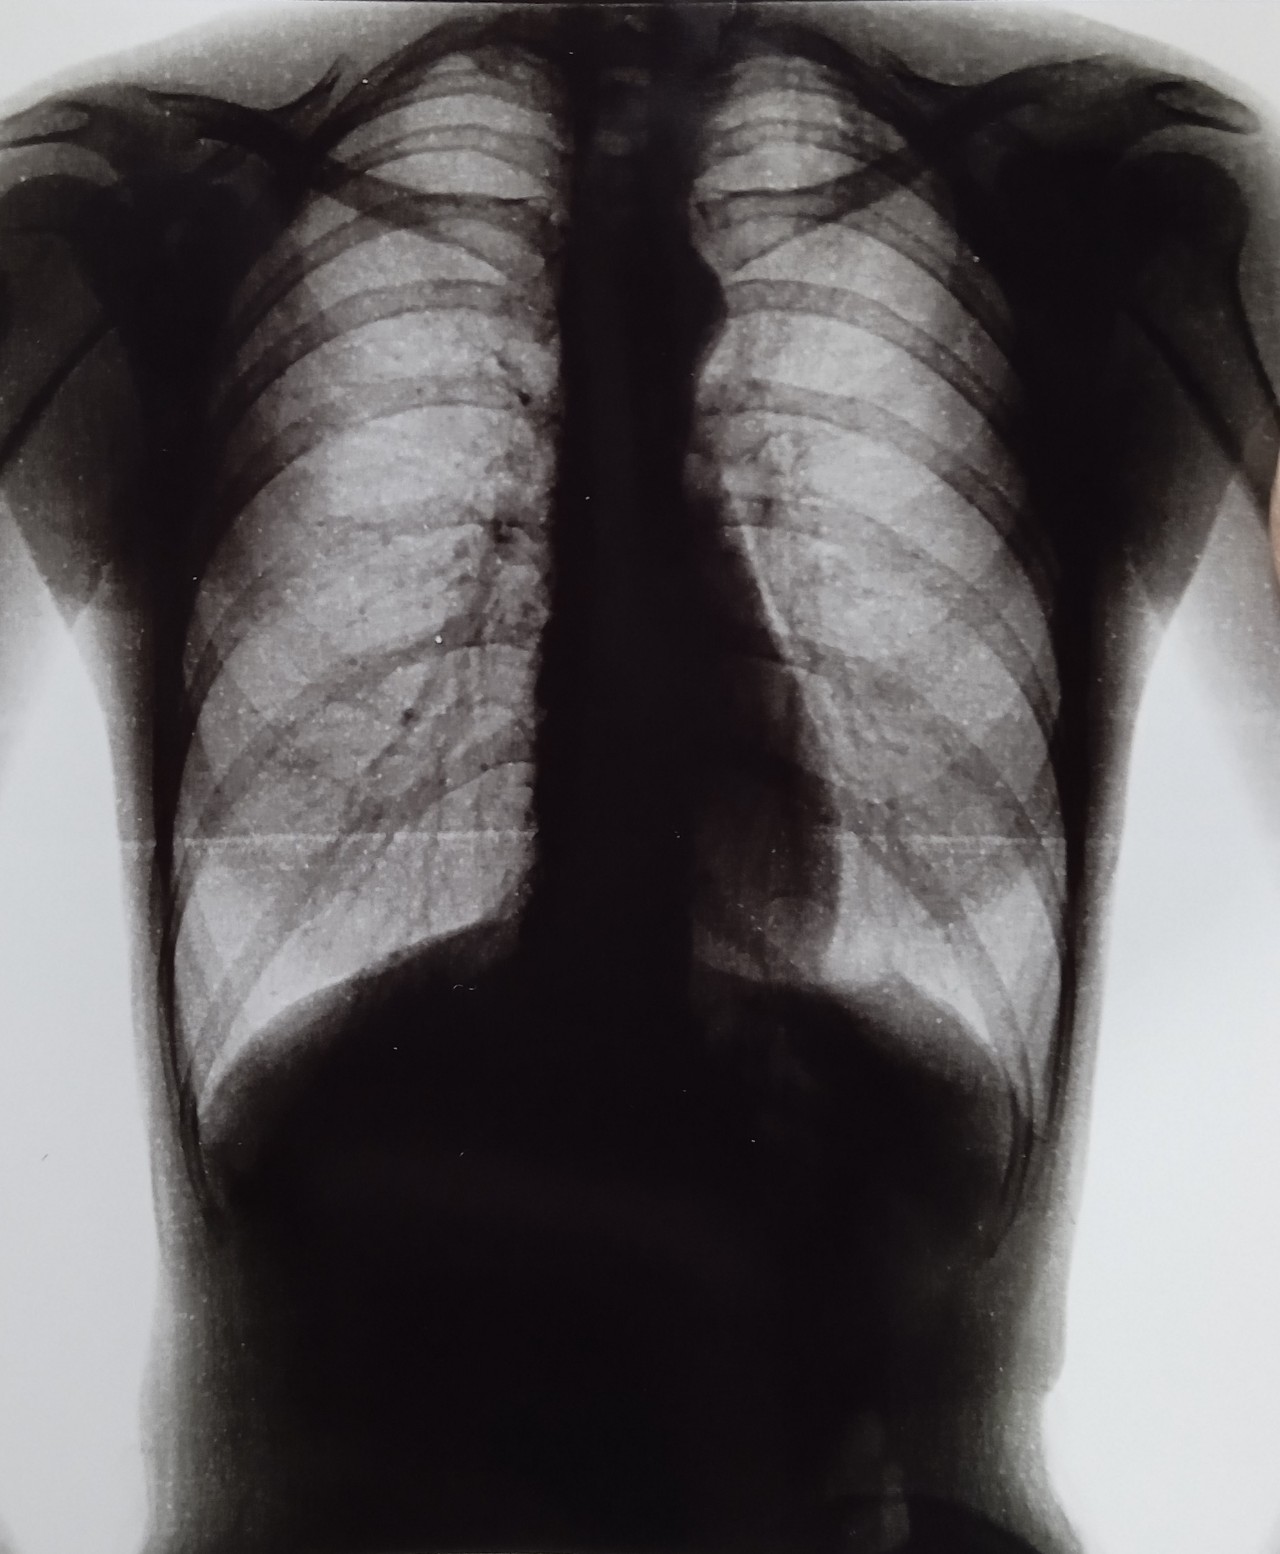

Снимок легких при туберкулезе является важным методом диагностики этого заболевания. На рентгеновских снимках можно увидеть изменения в легких, которые свойственны туберкулезу.

Фотографии снимков легких при туберкулезе

В данной статье представлены многочисленные фотографии снимков легких при туберкулезе, чтобы помочь вам понять, как выглядят изменения легких на рентгеновских снимках при этом заболевании.